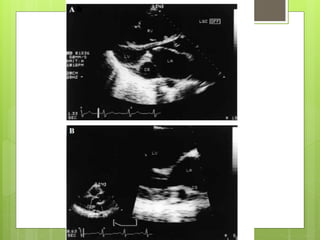

2-D ECHOCARDIOGRAPHIC

IMAGING OF CORONARY SINUS

CORONARY SINUS -2D ECHO